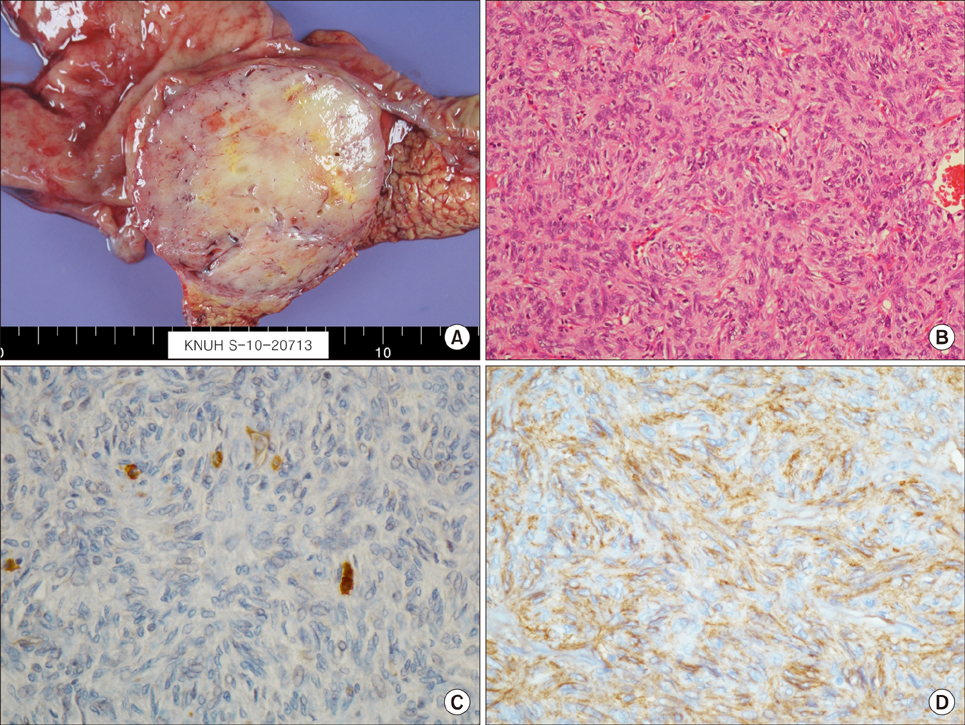

- Gastrointestinal tumors (GISTs) of the pancreas are extremely rare with limited individual case reports and small number of case series. Herein, we report a case of pancreatic extragastrointestinal stromal tumor (EGIST) along with literature review. A 64-year-old female patient was referred to us for treatment of an abdominal mass detected by ultrasonographic examination. The tumor was located in the periamullary region. Under a preoperative diagnosis of a duodenal GIST, we performed a pylorus preserving pancreatoduodenectomy for this lesion. Laboratory examination results were within normal ranges. On pathologic gross examination, the tumor measured at 7 cm in its greatest dimension almost entirely involved the pancreatic head. Its cut surface was rubbery and white. It was surrounded by a thin pseudocapsule and well demarcated. Histopathological examination of the specimen showed a cellular lesion with compressed pancreatic tissue at peripheral. Mitotic count was 5 per 50 high-power fields. Immunohistochemically, neoplastic cells were positive for antibodies against C-KIT (CD117), CD 34, and vimentin. However, smooth-muscle actin reactions with antibodies against S-100 or desmin were negative. Based on above findings, the tumor was finally diagnosed as GISTs originating from the pancreas. The patient has been followed up postoperatively for 72 months. There is no evidence of recurrence. Here we report this case of pancreatic EGIST presenting as a solid neoplasm along with literature review of cases previously described. Our review on pancreatic EGISTs is limited and insufficient to make a conclusion regarding its clinical features. Those manifested large masses tended to have an aggressive biological and clinical behavior. Thus, pancreatic EGISTs need to be carefully differentiated. Adequate surgical intervention is necessary for pancreatic EGISTs.